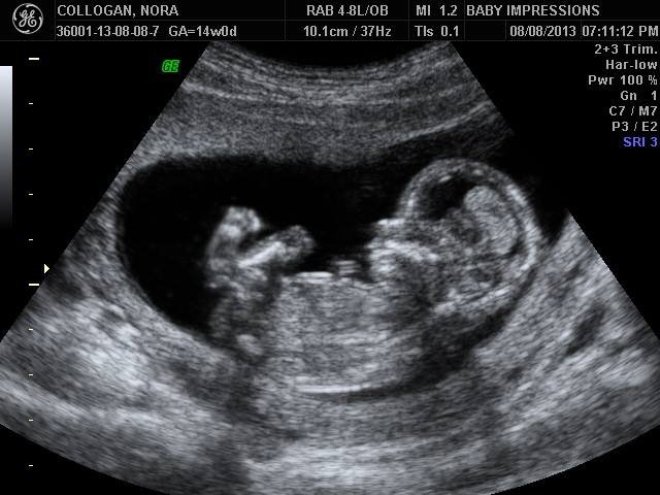

не знаю у моего такая фото когда трансвагинальным.. а когда по животу то в профиль лежит целиком...

а у вас как попой к пупку.

Он лежал просто на спине как у вас на фото. Сразу сфоткал и голову и писюн ))

Мне УЗИ делали когда, то было фото вот такое с боку. Но он как-то заводит датчик, что-то увеличивает, крутит вертит и получается вот такие ноги как в посте)) мне он тоже так показывал, только попка сверху, а ножки к низу)